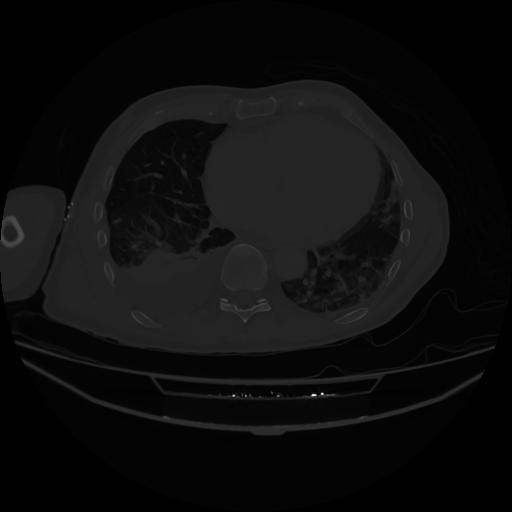

5 CUERPO,CE,Vol,1.0,CUERPO,,